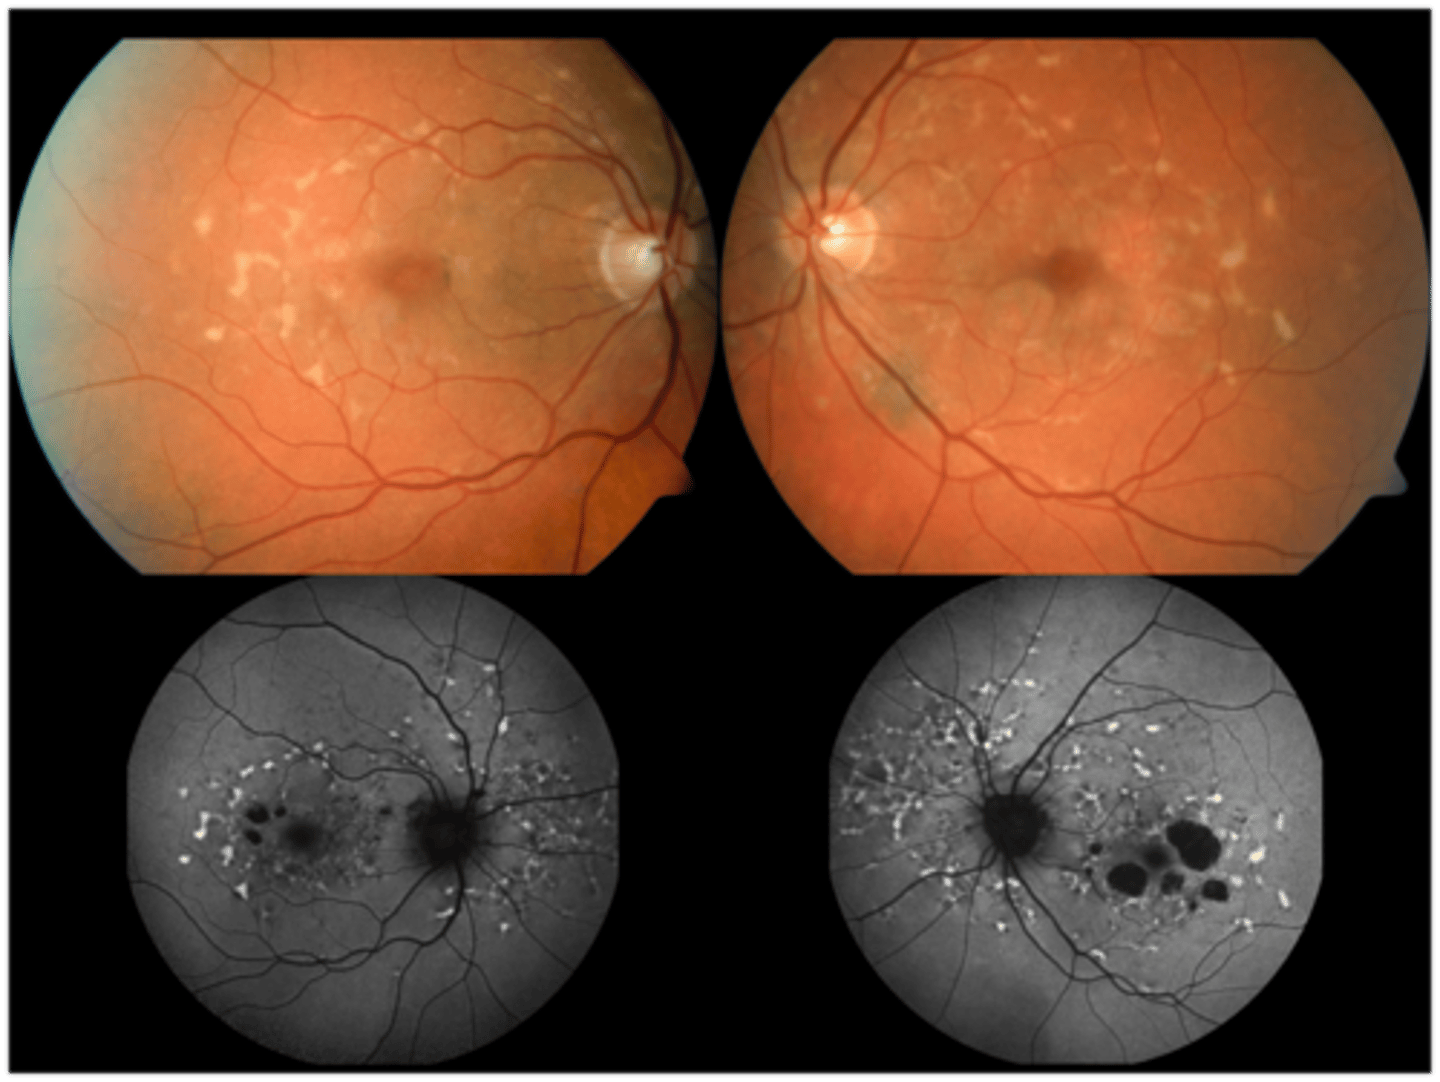

What findings of Leber's Congenital Amaurosis are seen here?

attenuated BV

peripheral pigmentary changes

FAF = peripheral hypopigmented spots and a ring of hyperfluorescence surrounding the fovea

macular atrophic lesion